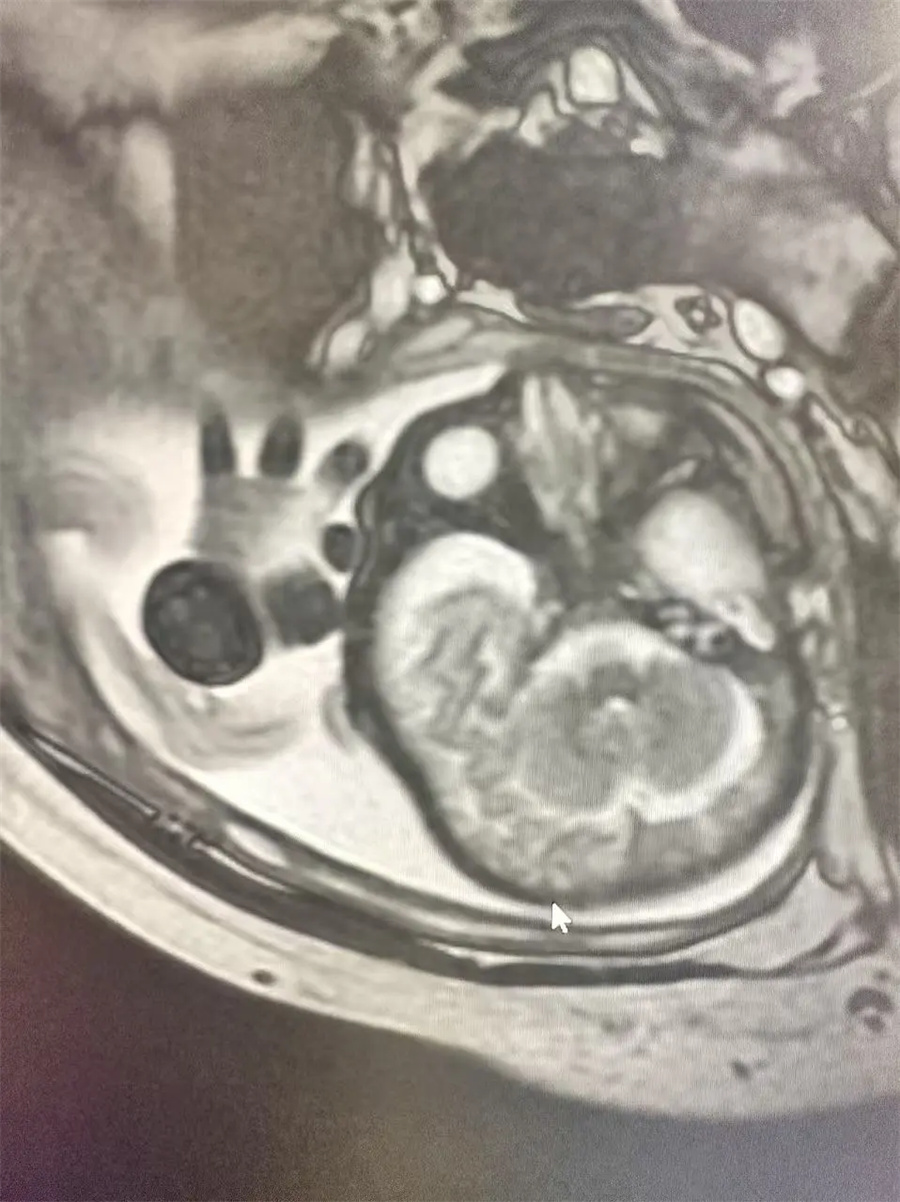

3.已经查出胎儿先天畸形、中枢神经系统异常,但不能判断是哪种病变。

如果出现上述情况,产科医生将会和孕妇充分协商并确认后,再补充一个MRI。MRI组织分辨率高,可以更好地显示内脏及肌肉结构,大大提高病变检出率;可以多方位成像,从三维空间观察人体组织结构,提高病变定位准确性;不受母体腹壁厚度、羊水量、肠管和胎儿体位、胎儿骨骼骨化与否的影响,可以进行大范围、多参数成像,能够清晰显示胎儿各个器官信号特点,获得更多胎儿信息,进而更加明确宝宝的健康状况。